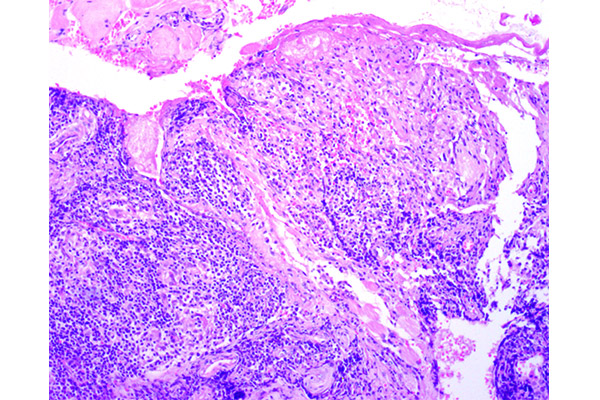

La característica más notable es un infiltrado inflamatorio denso y difuso que ocupa la dermis.

El infiltrado inflamatorio es intenso, a menudo respetando un «espacio» debajo de la epidermis (la zona de Grenz). Sin embargo, como en este caso puede estar ausente por la extensa ulceración.

Los microabscesos pueden alcanzar las capas más profundas del párpado, disecando las fibras musculares estriadas del orbicular de los párpados (FM).